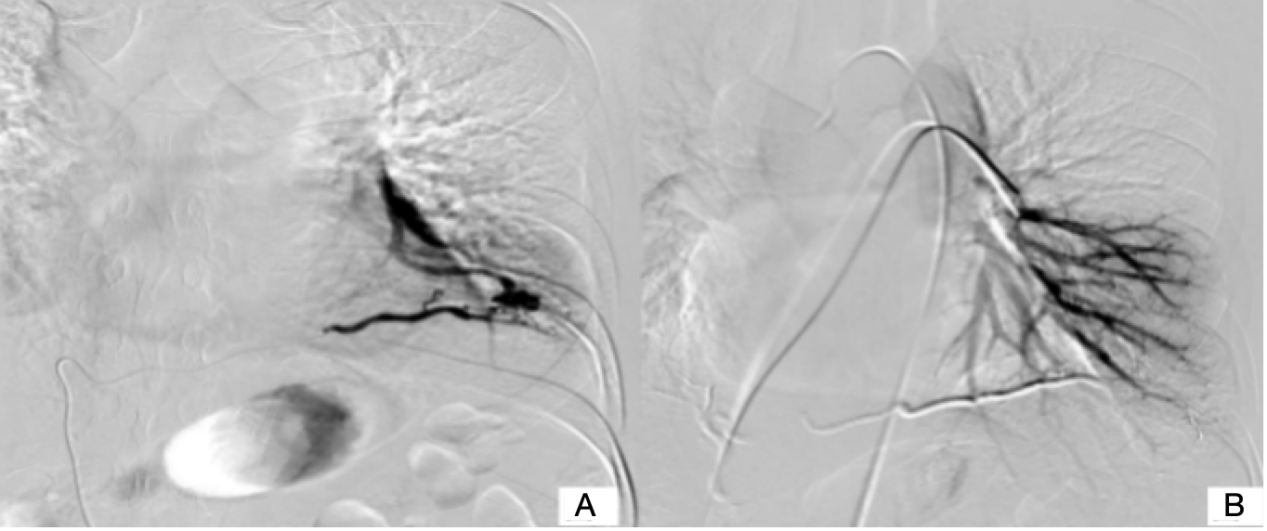

The patient refused the operation and had received embolization treatment. Two days later, we started the treatment course. Prior to embolization, vascular malformation was confirmed by selective angiography. The views have tortuous and thickened right inferior phrenic artery (Figure 1 C) and malformed anastomosis at the end of left inferior pulmonary artery display (Figure 1 D) but without obvious pulmonary vein (Figure 2 A). During the diagnostic angiography, 1.5 ml of iodized oil and 0.5 ml of tissue glue embolization were performed with a Super selective microcatheter. After embolism, there was no blood flow or a little blood flow (Figure 2 B) and soon the patient's symptom disappeared. He had simple misery in operation areas the first postoperative day, and the pain gradually ease. We consider this discomfort may related to surgical trauma. Then he was discharged from hospital after four days. No vascular abnormality was visible three and one half months later when a plain and enhanced CT were done. The patient reported minimal pain when pressure to the wound but no other symptoms.

Figure 1 (A) : CT pulmonary window showed a soft tissue density strip abutting on the oblique fissure in the left lower lobe. (B) A contrast-enhanced CT scan showed a malformed vascular mass and significantly thickened right phrenic artery. (C) Selective angiography of the right inferior phrenic artery. (D) Selective angiography of the left pulmonary artery.